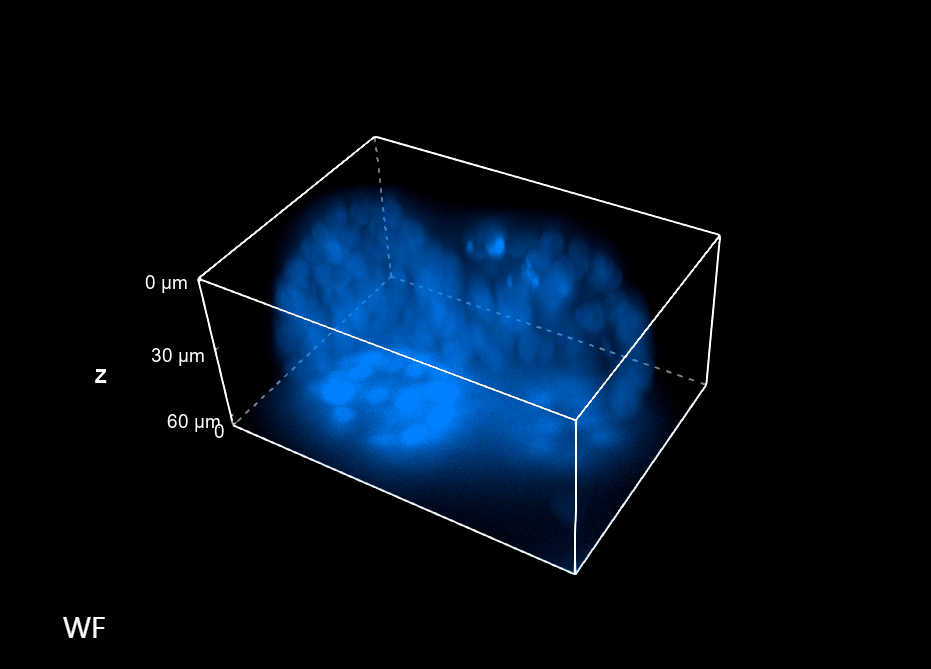

The imaging acquisition technology behind HCI requires a system capable of collecting many images in a short time; however, speed isn’t the exclusive requirement. Indeed, HCI is very often applied to 3D samples that best summarize the correct tissue physiology or pathology. Hence, for this type of application, it is essential to have a system that is also capable of achieving an axial resolution sufficient to resolve complex biological structures properly.

Especially where there is the need to make a morphological study of thick 3D structures, the common Widefield (WF) techniques risk giving an approximate view of the sample. In this context, Figure 1 compares two 60 um thick spheroids acquired with WF and confocal (CF) imaging modalities. It is therefore evident that due to a better Z sampling provided by the CF, two spheroids that otherwise would appear as a single large spheroidal structure can be better resolved and this is crucial when morphological studies are accomplished.

Figure 1: Comparison between WF and CF spinning disk volume views of 60 um spheroids. These images were acquired with a CFI Plan Apochromat Lambda D 60x oil objective (60x, Nikon, 1.42 NA and 0.15 mm WD).